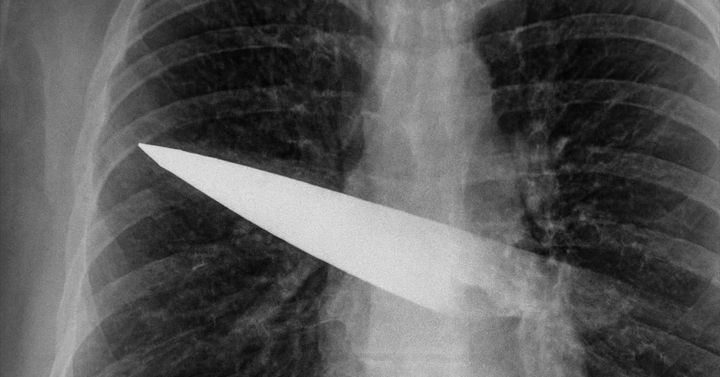

こちらは胸部にナイフが刺さっていることを示すX線画像

さらにCTスキャンでは、刃は背中の第5・6肋骨の間から体内に入り、胸の前面(第3・4肋骨の間)まで貫通していることが分かりました。